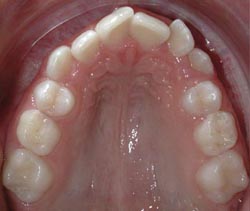

Engstand der Zähne, eine Frontalansicht |

Engstand bei einem Unterkiefer, eine Sicht

von oben (mit Sicht auf die Oberflächen,

lat. Facies [7]) |